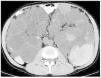

Los cálculos renales son otra causa frecuente de dolor agudo en los pacientes con PQRAD; se estima que aproximadamente un 20% de los pacientes los presenta. La composición de dichos cálculos es generalmente de ácido úrico y/o de oxalato de calcio. Los factores metabólicos predisponentes incluyen un bajo pH urinario, una baja concentración de citrato urinario y una excreción de amonio disminuida. Por otra parte, la estasis urinaria secundaria a la distorsión de la anatomía renal también puede estar implicada. Una TC abdominal con y sin contraste es la mejor técnica radiológica para detectar pequeños cálculos de ácido úrico que pueden ser muy tenues en radiografías simples. Las nuevas técnicas de TC con energía dual permiten diferenciar entre cálculos compuestos de ácido úrico y cálculos con contenido cálcico, una distinción importante para la elección de la terapéutica adecuada (figura 5 A y B). Los cálculos pueden ser difíciles de diferenciar entre calcificaciones de la pared de los quistes o intraparenquimatosas. Cuando solamente se obtiene una TC con contraste los cálculos pueden pasar desapercibidos.

Figura 5. Tomografía computarizada de energía dual que permite la caracterización de la composición de los cálculos renales.